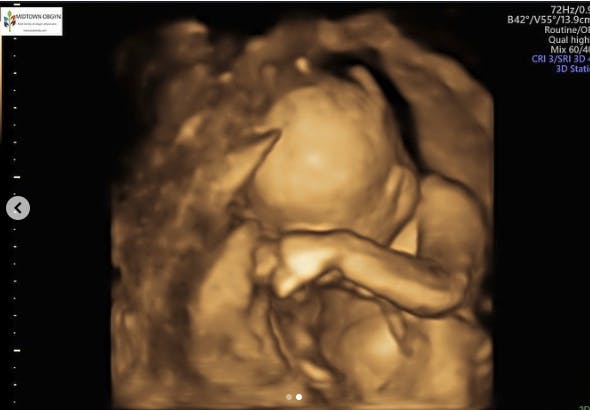

På Instagram fortæller den unge mor, at hun er gravid i 25. uge nu, og at hun i uge 23. fandt ud af, hendes lille pige ikke ville klare den.

– Jeg vidste, hvad jeg ville gøre. Jeg vidste, at jeg ville afslutte graviditeten. Min baby lider inde i mig, får anfald flere gange om dagen. Jeg kan mærke hver og en. Jeg vidste, at jeg ikke ville lade hende lide mere, fortæller Chloe på Instagram.